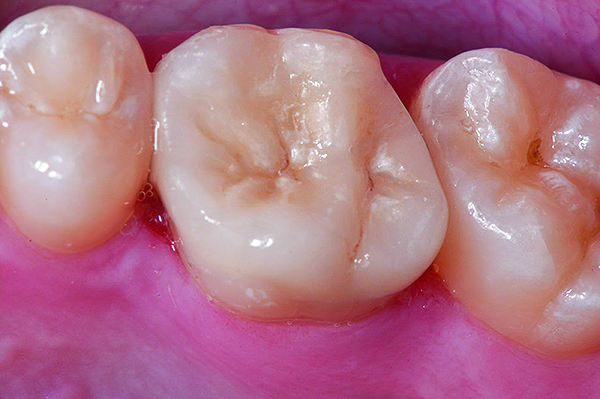

Fig 15. Machined CL-IIIb zirconia framework prior to coloration and final sintering (Fig 15); colorized and final sintered monolithic CL-IIIb zirconia restoration (Fig 16) (images courtesy of Enrico Steger/Zirkonzahn).

Figure 15

Fig 16. Machined CL-IIIb zirconia framework prior to coloration and final sintering (Fig 15); colorized and final sintered monolithic CL-IIIb zirconia restoration (Fig 16) (images courtesy of Enrico Steger/Zirkonzahn).

Figure 16